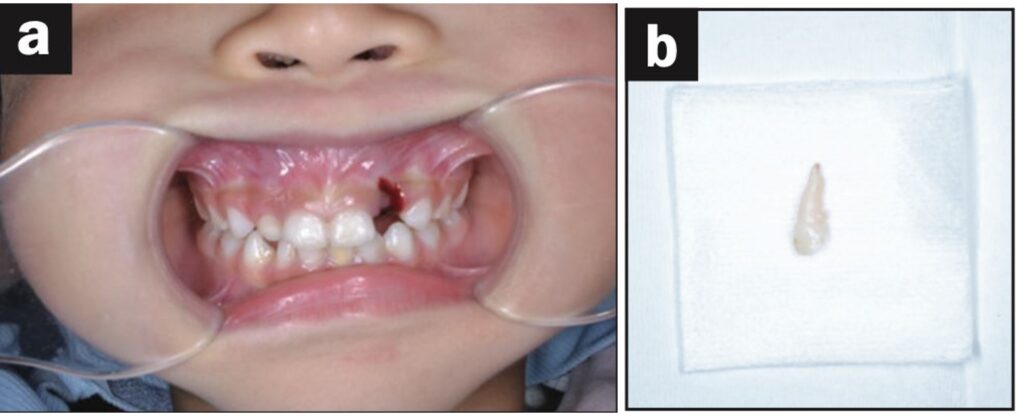

Bệnh nhân là một bé gái 5 tuổi bị ngã đè lên chai nước khi đang uống nước và bị bật răng cửa sữa bên trái ra ngoài. Nhân viên chăm sóc trẻ đã rửa răng bằng nước máy và làm sạch chất bẩn trên răng, loại bỏ màng nha chu.

Răng được đặt lại và cố định bằng composite quang trùng hợp, sau đó lấy dấu. Bệnh nhân quay lại phòng khám nha khoa 3 tiếng sau đó và nhận khay duy trì.

Dặn dò phụ huynh để cho bệnh nhân phải đeo hàm duy trì cả ngày trừ lúc đánh răng. Răng được kiểm tra sau 1, 7, 14 và 21 ngày và chụp X quang sau 28 ngày. Điều trị nội nha được thực hiện sau khi răng đã ổn định.

Quá trình theo dõi 12 tháng trong giới hạn bình thường (hình 1f).